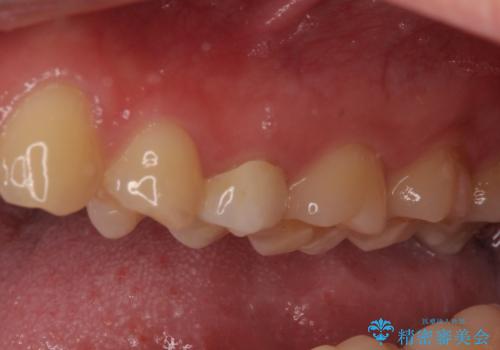

右上もう1本と左上は虫歯治療(セラミックインレー、セラミッククラウン)を行いました。

歯を引っ張り出したり、歯肉の手術の経過待ちの間に、患者様のご希望で他の歯の虫歯治療も行いました。

痛いところがなくなり、患者様には大変満足して頂きました。